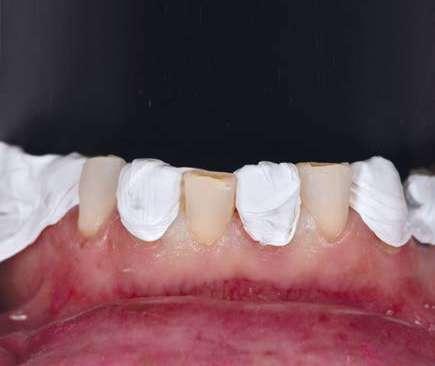

Presentación del caso clínico

A continuación, presentamos el caso clínico de una paciente con unos dientes mal posicionados y con una coloración acentuada sobre todo a nivel de los centrales que además presentaban extensas restauraciones antiguas de composite en interproximal cerrando diastemas que originalmente presentaba la paciente. Estos dientes necesitarán tener una preparación un poco más subgingival y también removido previamente todo el composite antiguo con el objetivo de camuflar este cambio de color y evitar zonas visiblemente no estéticas.

Además, lo combinaremos con unas carillas inyectadas inferiores también planificadas digitalmente y sin tallado, para crear una armonía y equilibrio con la parte superior.

En estos casos donde tenemos que camuflar sustratos oscuros o los dientes tienen una malposición severa haremos una preparación previa de los márgenes y zonas especialmente retentivas para mejorar la inserción de nuestras carillas. Por tanto, podemos beneficiarnos de las ventajas de la planificación digital, en cualquier caso, siendo necesario en los casos más complejos una preparación previa.

Como podemos observar la paciente tenía un sustrato muy desfavorable, con un color aproximado de A3,5 Vita.

Para la arcada inferior se optó por unas carillas inyectadas, completamente respetuosas con los tejidos, que nos permiten mejorar la apariencia de los dientes y dar así una mayor armonía con la parte superior. Al ser también planificadas digitalmente aseguramos que lo que colocamos en boca sea una fiel reproducción del diseño previamente aceptado por el paciente y el profesional.

En la arcada superior por el contrario se decidió poner unas carillas de disilicato para poder cubrir las expectativas de la paciente y ajustar el color al que ella deseaba, bajando casi en 5 tonos el color final. Se planificaron preparaciones digitales conservadoras.

La tecnología digital permite lograr el equilibrio de espesores ideal para cada caso, así como un eje de inserción adecuado. Todo esto permite dar una garantía de longevidad a las restauraciones planificadas.

En este caso se realizó una preparación previa a la preparación guiada en los márgenes y zonas interproximales, para camuflar el sustrato y dar una correcta inserción; y posteriormente se utilizaron unas guías de tallado diseñadas digitalmente para obtener los resultados precisos y predecibles que requería el caso.

La preparación previa junto a la preparación guiada, resultaron en un equilibrio ideal para los espesores mínimos que requería el caso. Se realizó una prueba en seco para valorar el ajuste final de las restauraciones.

Para cementar las carillas y evitar movimientos no controlados y una incorrecta cementación, utilizaremos una guía de posicionamiento simultáneo, esta guía no es de cementación en bloque ya que las carillas están perfectamente individualizadas. Únicamente sirven para llevar a la boca del paciente las carillas y cementarlas de una forma 100% segura, evitando el estrés que genera un posible movimiento durante la cementación y acelerando los tiempos de trabajo.

Consiguiendo así una perfecta adaptación de los márgenes de las restauraciones y la sensación de naturalidad e integración que se observa en la imagen final.

Como se puede observar en la imagen comparativa, la planificación se reproduce de una forma fiel a lo que se había planificado y aceptado por la paciente. Por tanto, no es una técnica susceptible al operador, que se realiza controlando mucho mejor los tiempos y los resultados obtenidos.